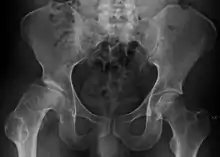

| Radiograph of a person with Legg–Calvé–Perthes disease | |

X-rays of the hip may suggest and/or verify the diagnosis. X-rays usually demonstrate a flattened, and later fragmented, femoral head. A bone scan or MRI may be useful in making the diagnosis in those cases where X-rays are inconclusive. Usually, plain radiographic changes are delayed six weeks or more from clinical onset, so bone scintigraphy and MRI are done for early diagnosis. MRI results are more accurate, i.e. 97–99% against 88–93% in plain radiography. If MRI or bone scans are necessary, a positive diagnosis relies upon patchy areas of vascularity to the capital femoral epiphysis (the developing femoral head).[11]